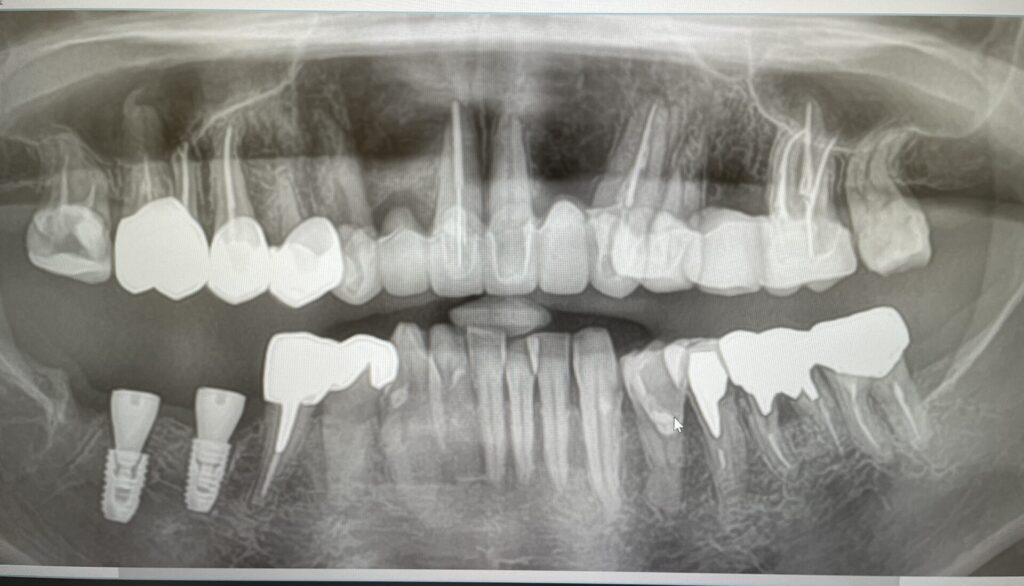

レントゲンを撮ることで、見えない部分の歯の内部や顎の骨の状態が観察できます。

セラミック本留前の仮歯でのレントゲン写真です。下の歯は破折があり抜歯してインプラントをしています。